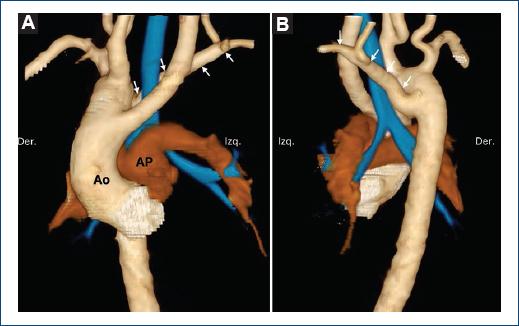

El arco aórtico circunflejo (Fig. 3), presente en el 8.1% de los casos, se presentó con y sin conducto arterioso (3.6% y 4.5%, respectivamente). Hay otras variables con respecto a la posición del arco aórtico y de la aorta descendente; de estos, el subtipo más frecuente fue el de aorta circunfleja con arco aórtico izquierdo, aorta descendente derecha y divertículo de Kommerell sin conducto arterioso (3.6%).

Figura 3 Arco aórtico circunflejo. Reconstrucciones volumétricas a partir de tomografía cardiaca en vista anterior (A), lateral izquierda (B) y posterior (C). Paciente de 1 año con arco aórtico circunflejo y divertículo de Kommerell (asterisco), en el que se observan un remanente del conducto arterioso (flecha), formando un anillo incompleto, y un origen aberrante de la subclavia izquierda. En azul se representa la vía aérea. Ao: aorta; AP: arteria pulmonar.